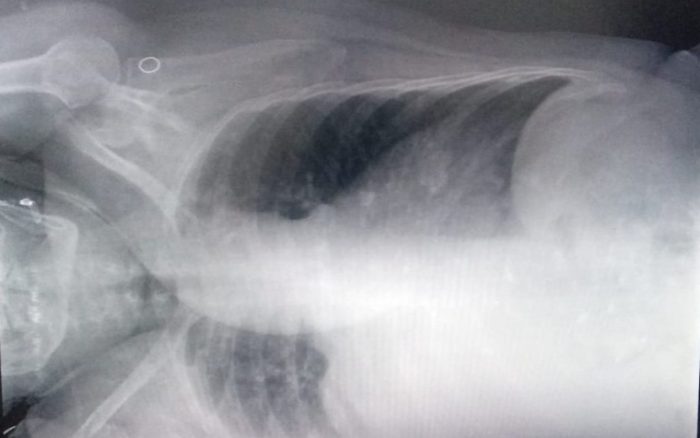

Sônia Maria de Lima de Souza, de 62 anos, está internada desde o dia 25 de julho na UPA Norte de Ribeirão Preto, por conta de um derrame pleural. De acordo com a filha da paciente, Kelly Aparecida Souza, a mãe está consciente, mas com dores e dificuldades para respirar.

“Desde que foi diagnosticada com água no pulmão, ela está internada aguardando por uma vaga. Ela está entrando em desespero”, comentou Kelly.